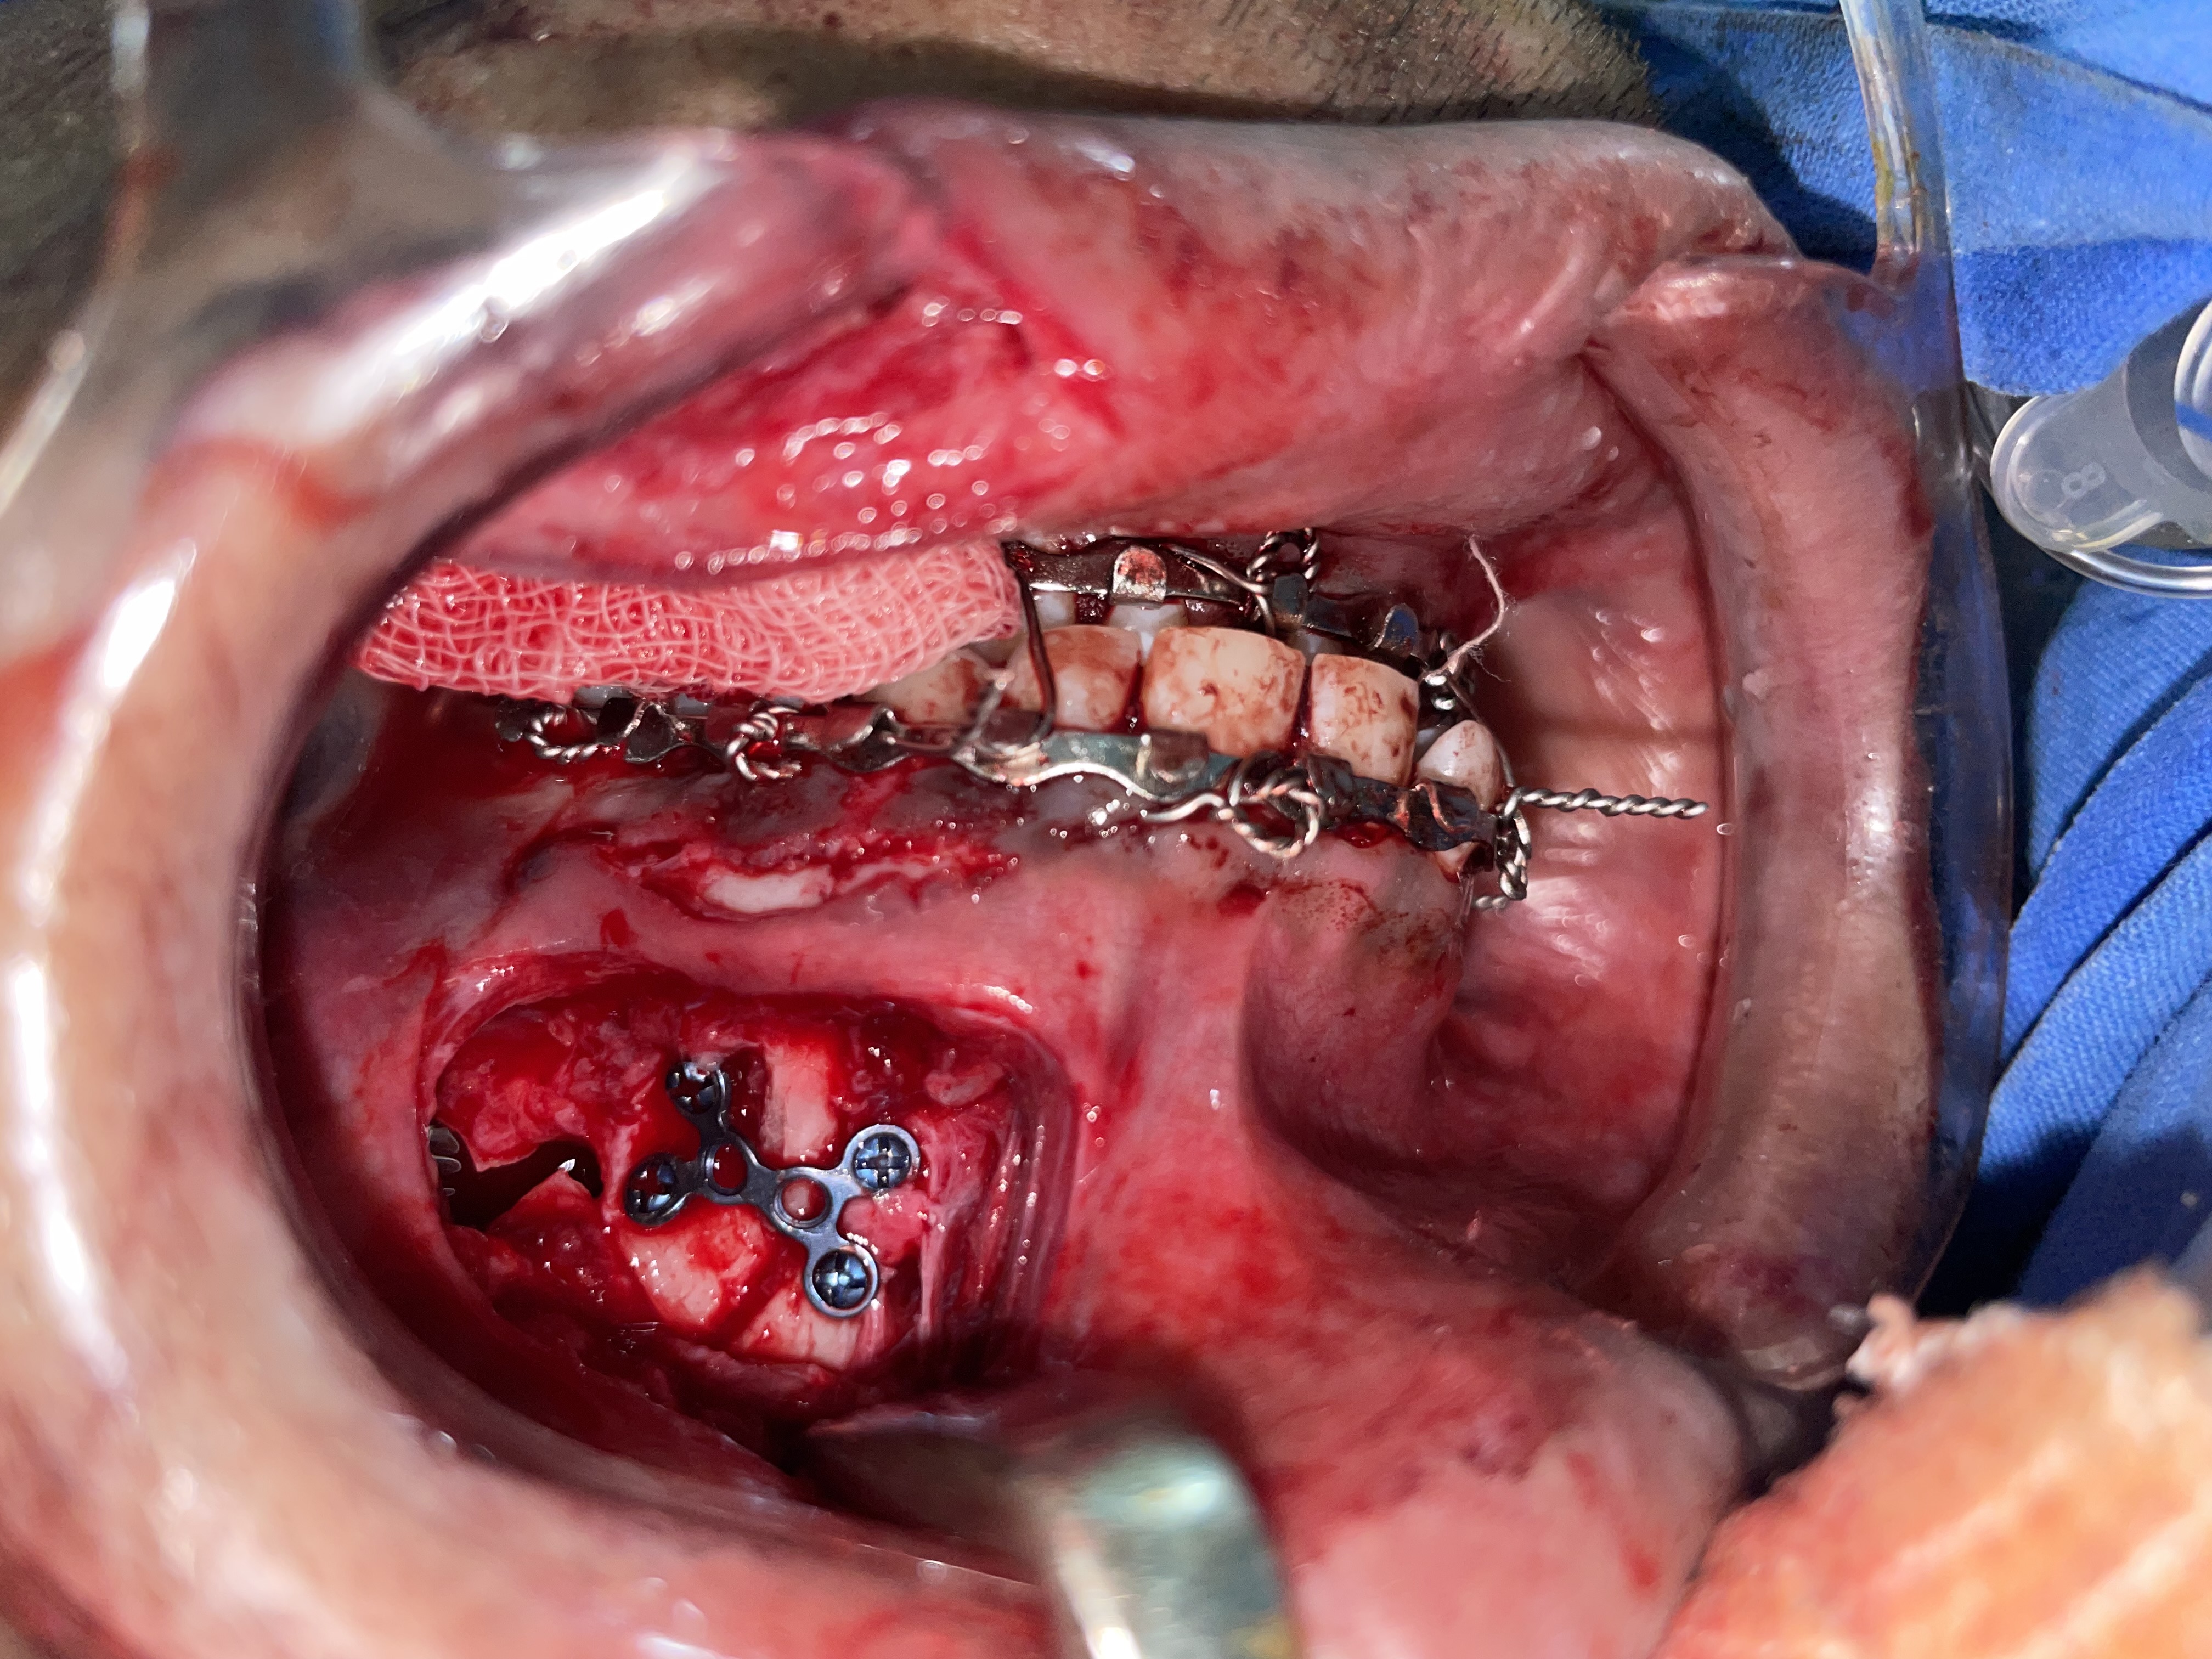

Mandibular Fracture Fixation focuses on restoring anatomical bone alignment, maintaining a proper dental occlusion (bite), and stabilizing the jaw for functional recovery. Before treatment, patients face severe pain, difficulty speaking or swallowing, and potential permanent facial deformity or malocclusion. After surgery, patients benefit from stable internal fixation, restored jaw function, and the ability to return to a normal diet and oral hygiene routine.